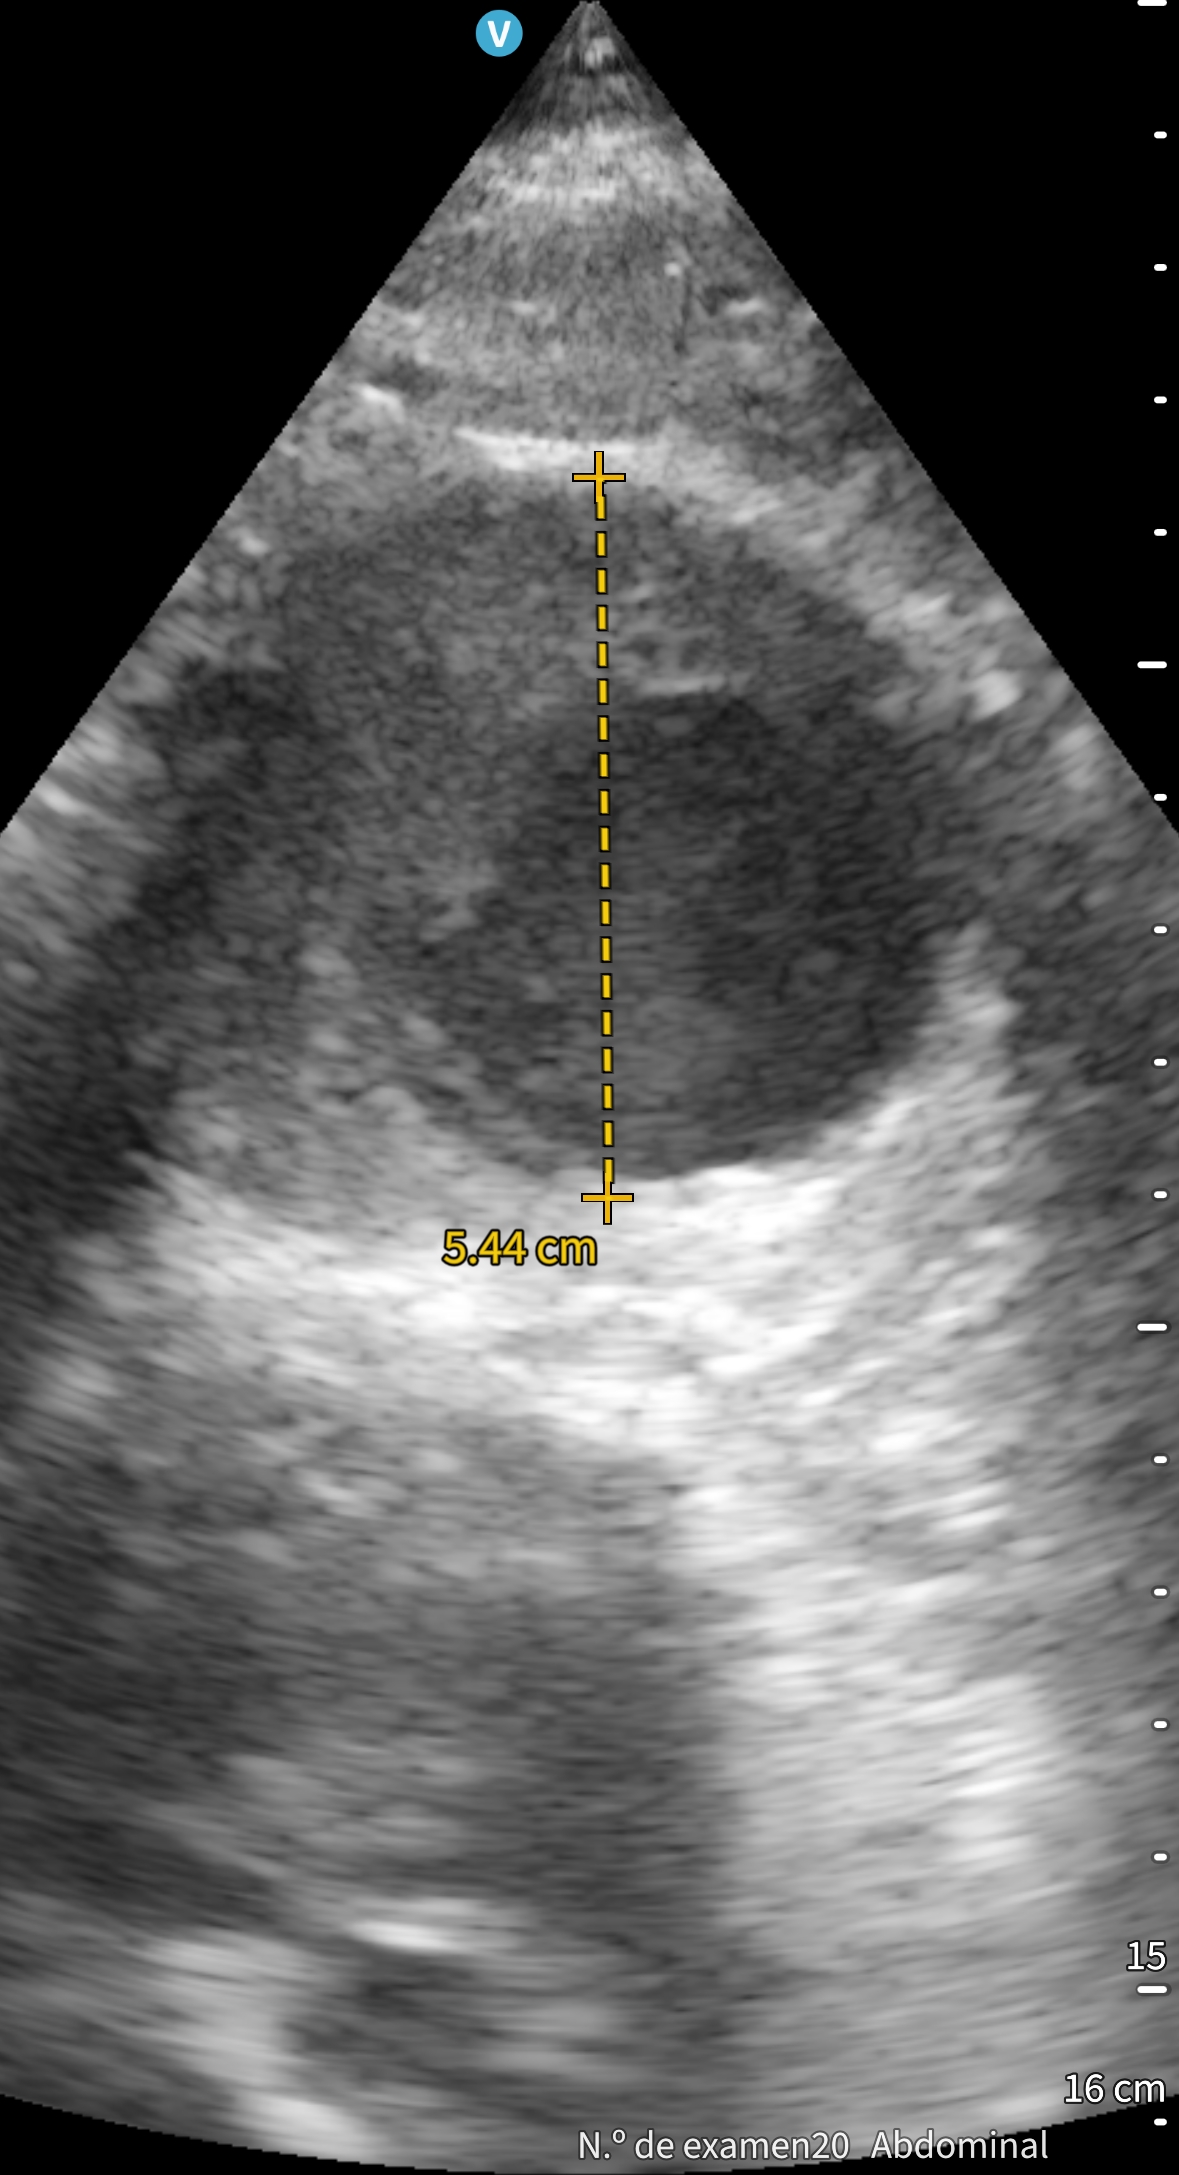

Tras finalizar una sesión de diálisis desarrolla hipotensión sintomática y dolor lumbar. A su llegada a urgencias presenta TA 60/40 mmHg, palidez mucocutánea y exploración abdominal anodina. Se inicia fluidoterapia. Ante la sospecha de rotura aneurismática se realiza ecografía a pie de cama, que muestra aneurisma de aorta abdominal con trombo mural irregular y luz permeable reducida, sin signos de rotura, permitiendo descartar una emergencia tiempo-dependiente. El angioTAC urgente confirma la ausencia de disección o extravasación, aunque evidencia crecimiento aneurismático respecto a estudios previos. Analítica sin anemia aguda, ligera leucocitosis y troponinas discretamente elevadas sin ascenso dinámico. Evoluciona favorablemente con recuperación tensional y resolución del dolor.

La ecografía clínica a pie de cama resultó fundamental para descartar de forma rápida una rotura aneurismática y dirigir el manejo inicial. Este caso demuestra su valor como herramienta resolutiva, segura y accesible en urgencias, reforzando la capacidad diagnóstica y la toma de decisiones del profesional de Medicina de Familia.